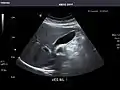

Liver

Liver: Diffusely homogeneous and normal in echogenicity. No focal mass or contour nodularity. No intrahepatic biliary ductal dilatation.

In patients with deranged liver function tests, ultrasound may show increased liver size (hepatomegaly), increased reflectiveness (which might, for example, indicate cholestasis), gallbladder or bile duct diseases, or a tumor in the liver.